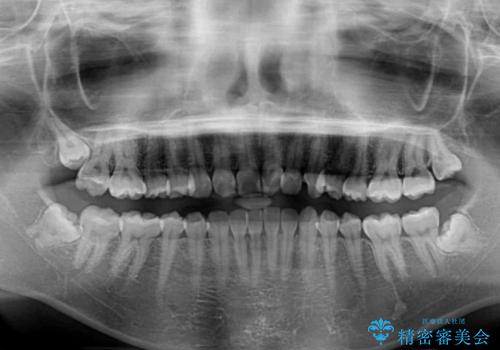

- 前歯の歯並びと虫歯を気にして来院された患者様です。

上下前歯の歯列不正はインビザラインにより歯列を整え、その後に、前歯5本をオールセラミッククラウンにて補綴治療することとしました。